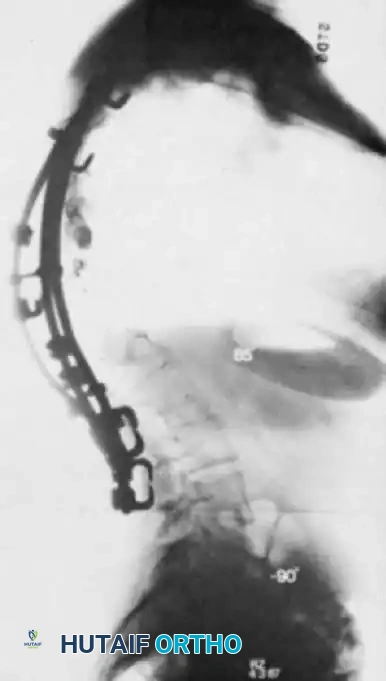

Fig. 41-16 Postoperative lateral radiograph showing restoration of lumbar lordosis and global sagittal balance. Note the robust pelvic fixation utilizing iliac screws extending distal to the sacrum.

Modern techniques primarily utilize:

* Iliac Screws: Placed through the PSIS down the iliac shaft towards the sciatic notch. Requires offset connectors to link to the main rod.

* S2-Alar-Iliac (S2AI) Screws: The current preferred technique. The starting point is midway between the S1 and S2 foramina, crossing the SI joint into the ilium. S2AI screws are in-line with the main lumbar rod, eliminating the need for offset connectors and reducing implant prominence.